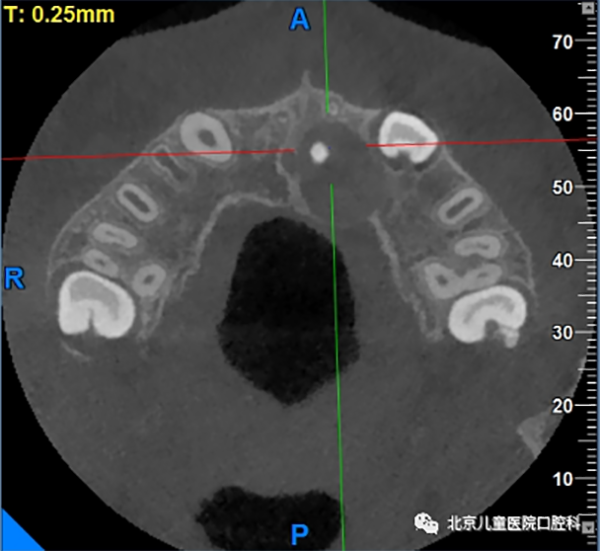

多生牙,又叫额外牙,是正常牙列以外的牙齿,发生的原因与遗传和发育障碍相关,通常在替牙期被发现,主要表现为萌出一颗畸形牙,或者新萌出的恒牙之间间隙过大,那多生牙有什么危害呢?

影响恒牙的发育和排列

多生牙可发生在牙弓任何位置,多见于上颌前牙区,通常会占用正常牙齿在牙列中的位置,破坏正常的牙弓形态,同时,由于不具备正常牙齿的外形而缺少与正常牙齿的邻接,容易造成食物嵌塞和滞留,导致牙龈组织发炎甚至引起龋齿的发生。更有甚者,占用了正常恒牙萌出的空间,挡了正常恒牙的“路”,使得正常恒牙无法顺利萌出。